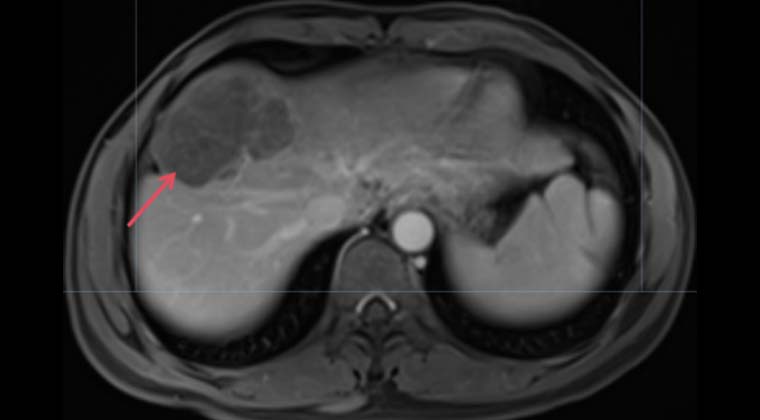

Пациент: мужчина, 41 год

Гепатоцеллюлярная карцинома, стадия BCLC C / CNLC IIIa

Симптом: боль в животе

Диагноз: 09-21 PET-CT выявило крупное образование в правой доле печени

11-16: Контрольное обследование после двух циклов интервенционной инфузионной химиотерапии показало значительное уменьшение очага в правой доле печени.

(Изображение после лечения)